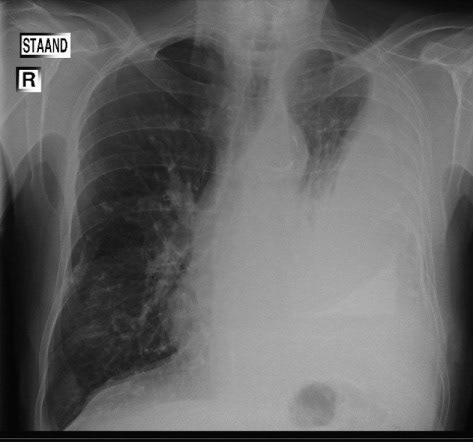

Pleuraal mesothelioom: ontstaat in het borstvlies en is de meest voorkomende vorm.

De ziekte ontwikkelt zich vaak langzaam, maar wordt meestal pas in een vergevorderd stadium ontdekt, waardoor behandelmogelijkheden beperkt zijn.

Het stadium van de ziekte: vroege detectie kan de prognose verbeteren, maar mesothelioom wordt vaak pas in stadium III of IV gediagnosticeerd.